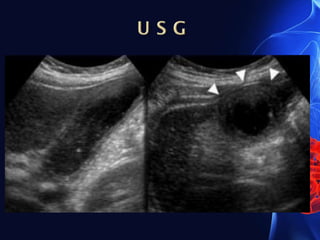

 Ultrasound : The mainstay of imaging in cholecystitis

• Gallbladder wall thickening (>3 mm), which may be poorly

defined.

• Impacted calculi in the gallbladder neck or cystic duct.

Gallstones are visualized as echogenic foci with posterior

acoustic shadowing.

• Biliary sludge may be seen as echogenic debris layering in

the gallbladder.

• Pericholecystic fluid.

• Positive sonographic Murphy’s sign